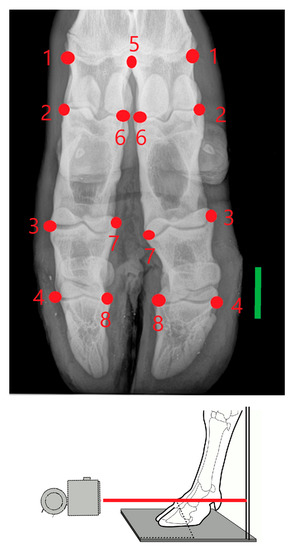

2. Materials and Methods

- Hoey, S.E.; Biedrzycki, A.H.; Livesey, M.J.; Drees, R. Radiographic anatomy of juvenile bovine limbs. Vet. Rec. 2016, 179, 546. [Google Scholar] [CrossRef]

- Rohlf, F.J. The tps series of software. Hystrix 2015, 26, 9–12. [Google Scholar] [CrossRef]

- Rohlf, F.J. Digitalized landmarks and outlines. In Stony Brook: Department of Ecology and Evolution; State University of New York: New York, NY, USA, 2010. [Google Scholar]

- Bookstein, F.L. Morphometric Tools for Landmark Data: Geometry and Biology; Cambridge University Press: Cambridge, UK, 1991. [Google Scholar]